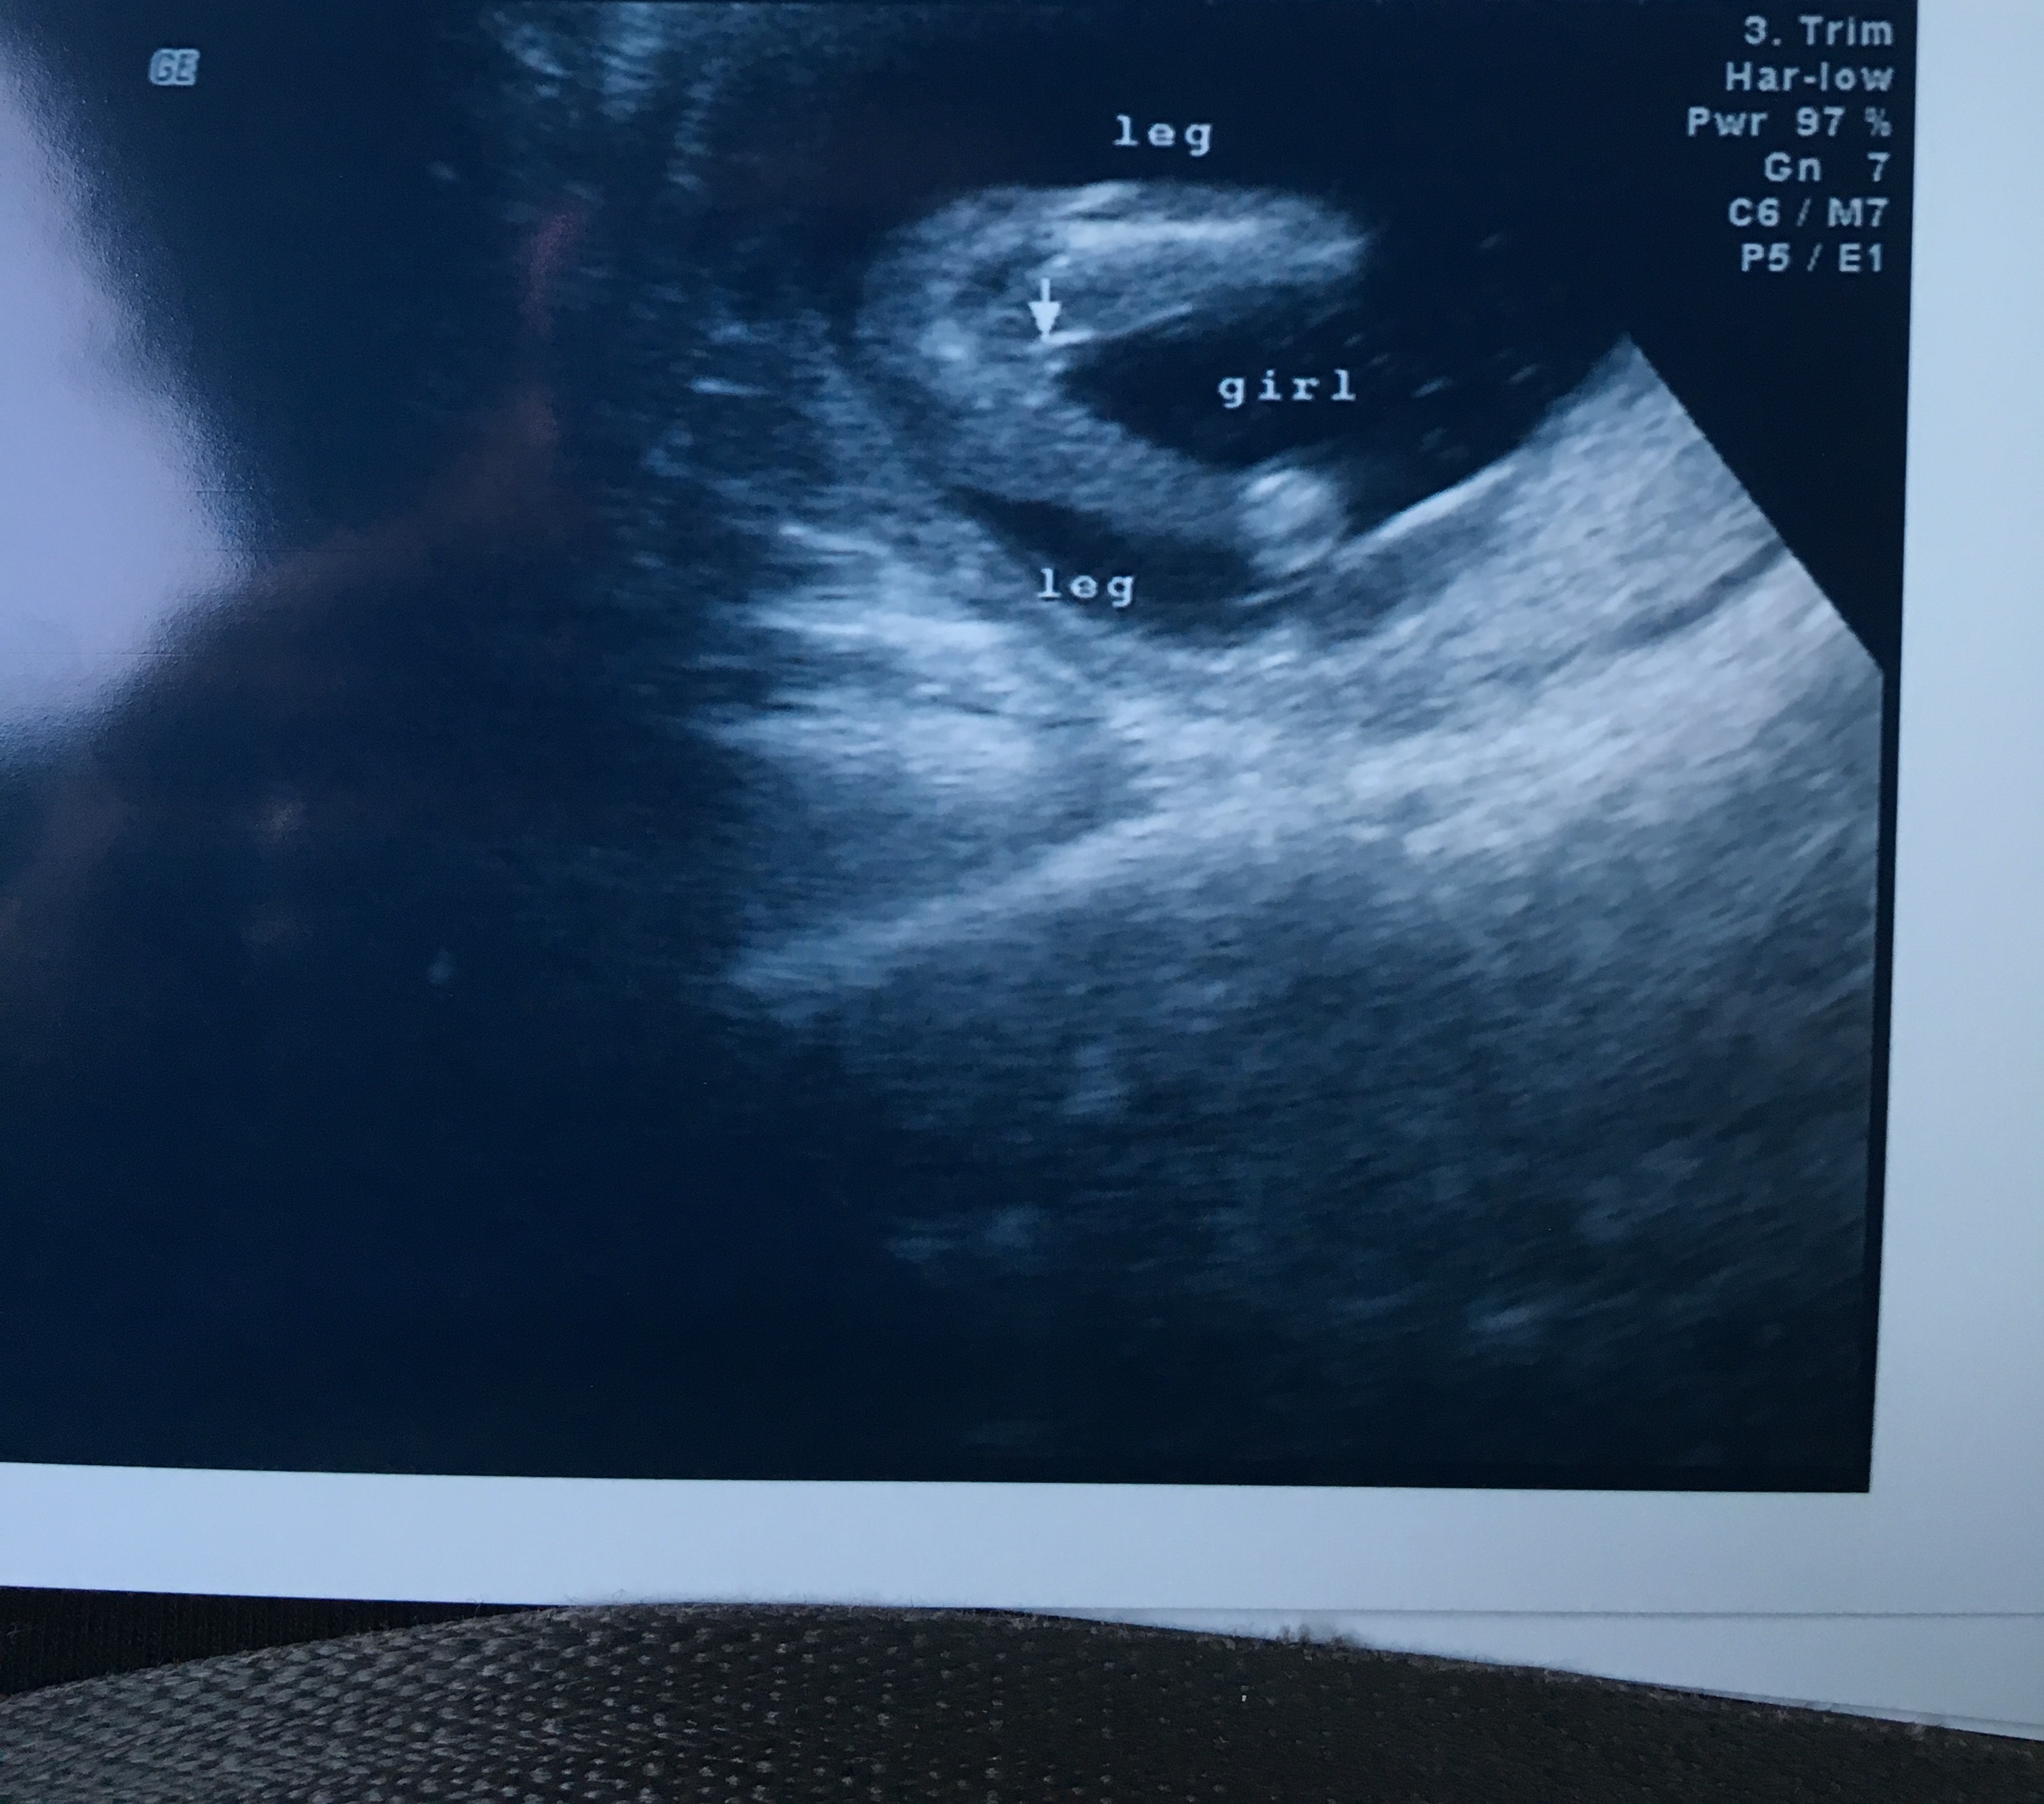

Attachment 32527. is this for sure a girl? had ultrasound done at 15 weeks 6 days!

I think so.. :ballerina: